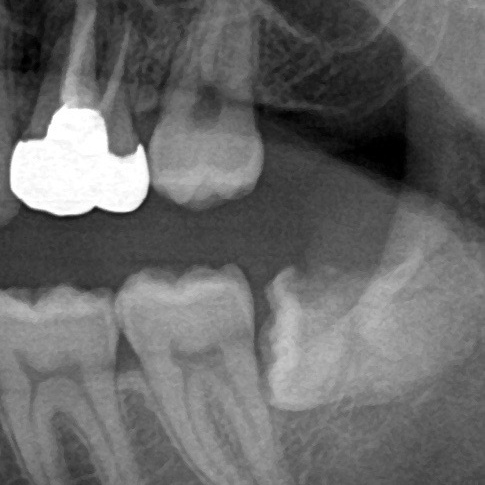

親知らずが斜めや横を向いていて、まっすぐ生えていない場合です。歯ブラシが届きにくいので、磨き残しからむし歯や親知らずの周囲の炎症が起こります。

また注意が必要なのは、7番目の歯(第二大臼歯)の後ろの方に深い歯周ポケット(注1)があると、親知らずがまったく見えず歯肉に隠れていてもバクテリアに感染してしまう場合があります。こちらも歯を抜くことが必要になります。